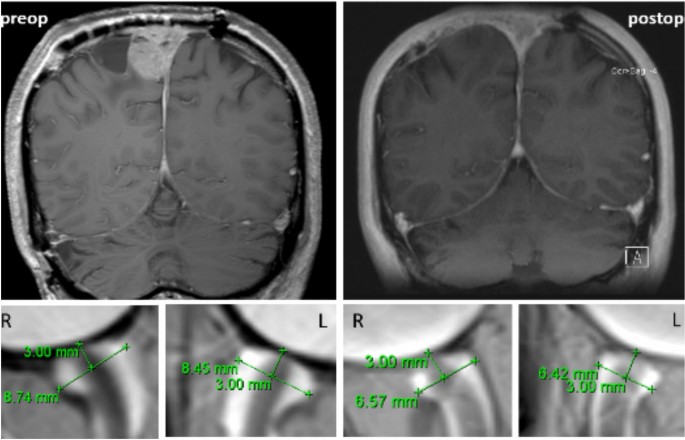

MRI-based measurements of the ONSD were conducted as previously described9 and as illustrated in Fig. 1.

The optic nerve appears hypointense and is surrounded by the hyperintense cerebrospinal fluid-filled optic nerve sheath. ONSD was measured in the axial plane 3 mm behind the optic nerve papilla. The massive dilatation of the optic nerve sheaths, in this case, improved postoperatively, although the values are still above 6. This highlights the importance of establishing ONSD measurements early in monitoring to assess patient-specific dynamics.

The mean values of the left and right ONSD values were calculated for further analysis and statistics. T2-weighted MRI sequences with thin slices of less than 3 mm were used at the initial and final presentations and just before and after surgery (at least 3 months before and after the procedure). A total of 403 measurements were taken by one experienced rater and independently verified for consistency by two other experienced investigators. Both internal and external MRI data sets were used. The total follow-up for ONSD measurements and clinical evaluation was 68 ± 67 months before and 27 ± 35 months after surgery.